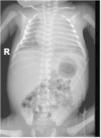

Ingresó en la unidad de cuidados intensivos, evidenciándose coagulopatía, colestasis y trombocitopenia mantenida a pesar de múltiples transfusiones. Los cultivos y serologías fueron negativos. En el frotis de sangre se evidenciaron linfocitos vacuolados. La radiografía y la ecografía posnatal mostraron hepatoesplenomegalia (fig. 3).